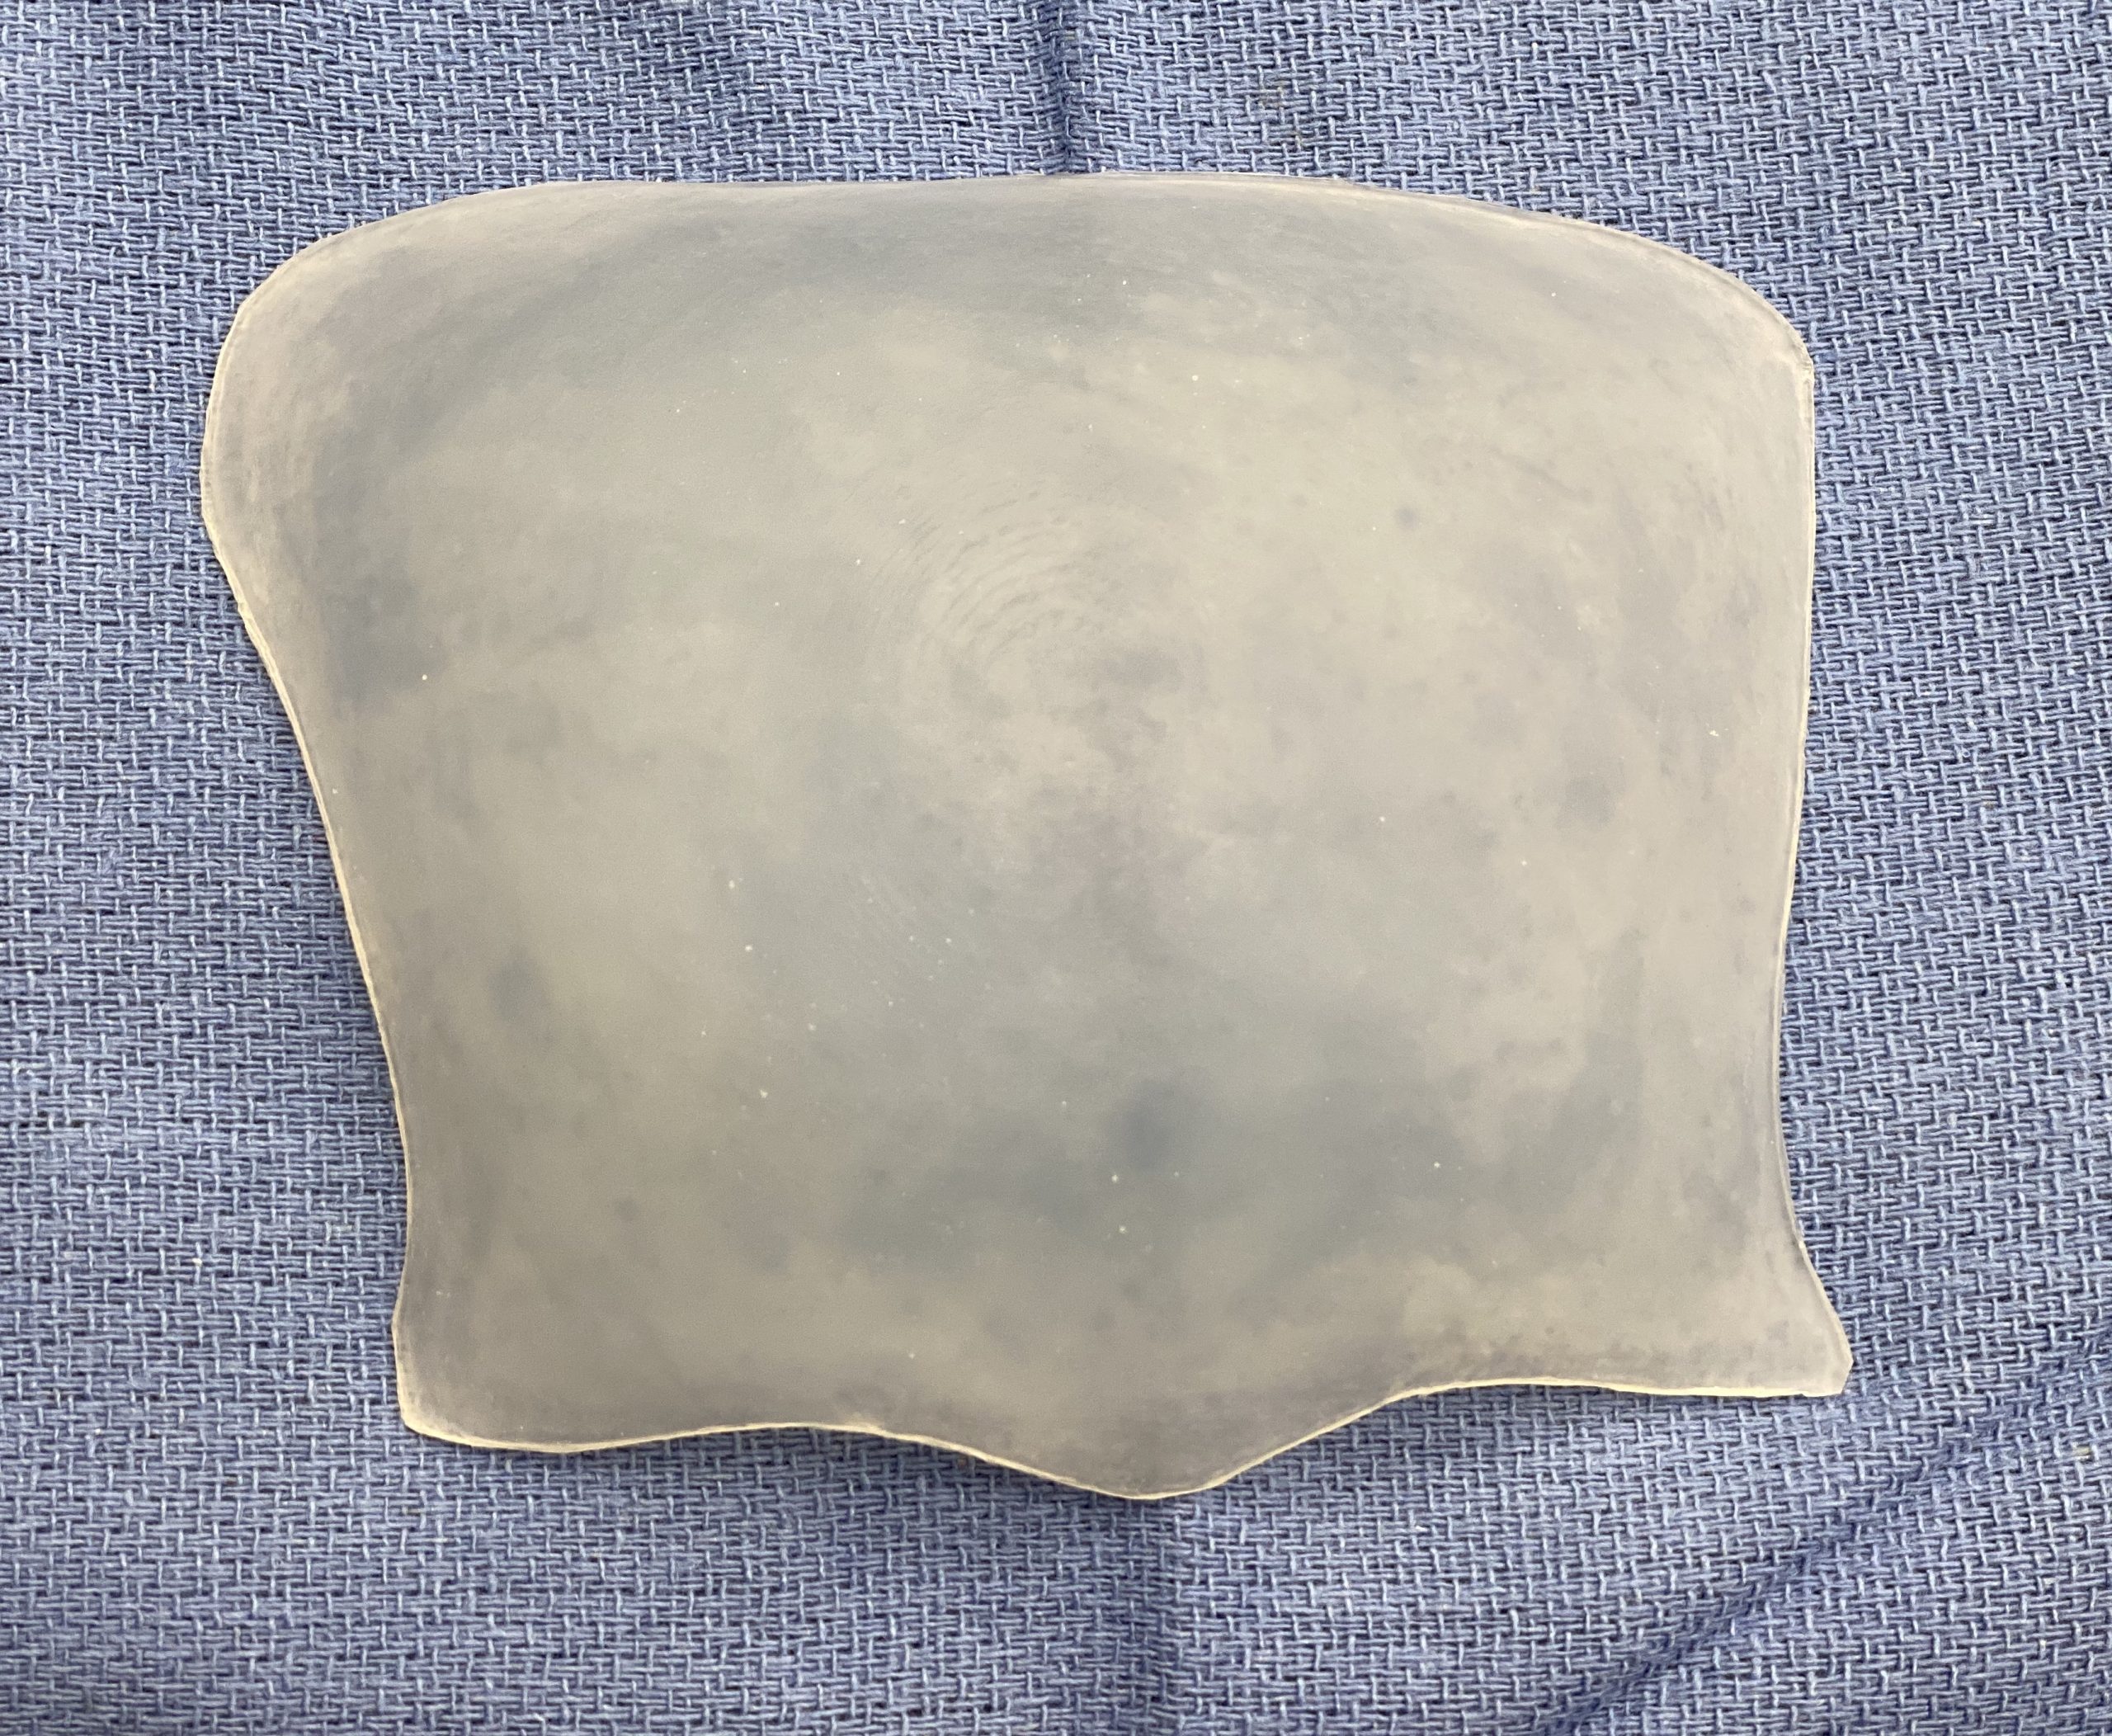

Desire for augmentation of flat back of the head that developed after wide excision and skin grafting of chronic scalp skin infections. This actually represented a loss of scalp thickness rather than a bone deficiency.

Occipital skull augmentation using a custom made implant designed from a measured template overlay on the depressed scalp area. Technically this was a 'scalp augmentation' using a bone-based implant.

Desire for augmentation of flat back of the head that developed after wide excision and skin grafting of chronic scalp skin infections. This actually represented a loss of scalp thickness rather than a bone deficiency.

Occipital skull augmentation using a custom made implant designed from a measured template overlay on the depressed scalp area. Technically this was a 'scalp augmentation' using a bone-based implant.